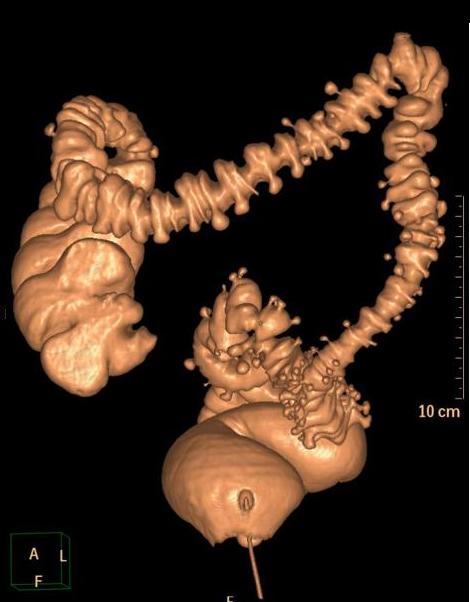

Diverticulose colique :

Image de coloscanner du cardre colon . La situation

des diverticule en voyaient sur 3D image .